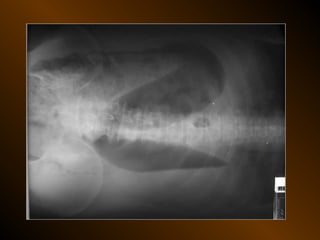

CĂNG GIÃN ỐNG TIÊU HÓA

• Căng giãn dạ dày

• Căng giãn tá tràng

• Căng giãn ruột non

• Căng giãn đại tràng

• Căng giãn ruột non lẫn đại tràng

• Nguyên nhân

• Cơ học : loét, ung thư, xoắn, bezoar

hẹp miệng nối, lồng ruột

• Không cơ học : toan máu, ure máu cao

• cắt tk X

• heroin